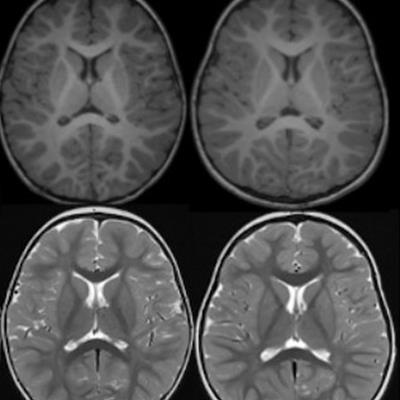

Deep learning helps radiologists predict pediatric myelin maturation age #radiology #ImagingAI bit.ly/44L2kQP